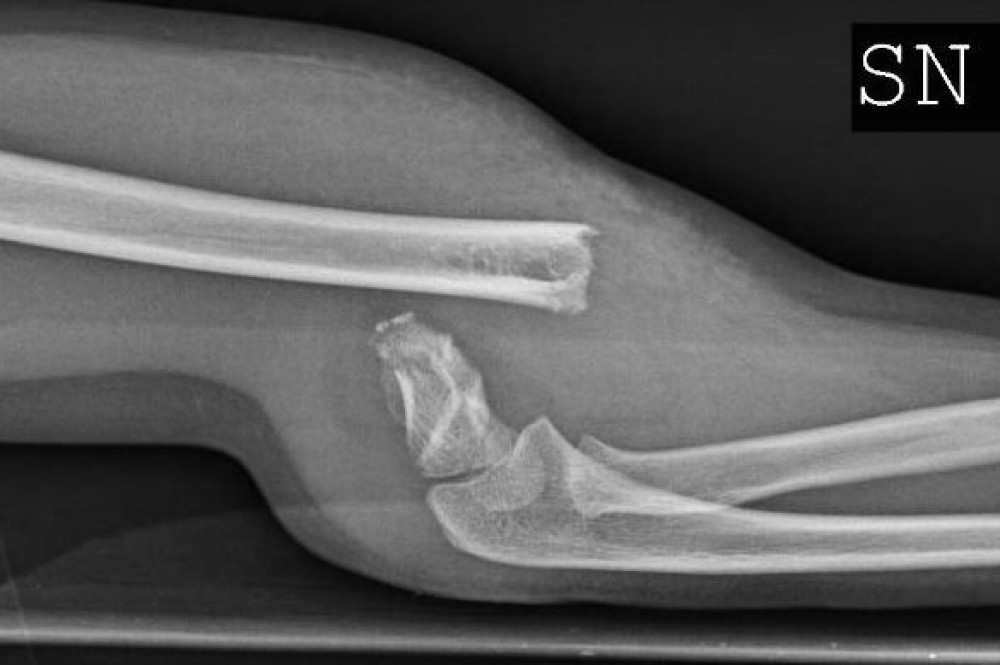

Il traumatismo del gomito è quasi sempre una frattura esposta perché normalmente la forza che produce le fratture dell'omero distale sono importanti. Normalmente è causata da una lesione, quando il gomito è sottoposto a un forte impatto, in seguito a. Le fratture del braccio o del gomito sono un evento abbastanza frequente che implica la rottura di una o più ossa del braccio:

Se si tratta di una frattura scomposta si può. Sintomi gomito che si gonfia immediatamente dopo il trauma e il dolore è così forte che non si riesce a compiere nessun movimento; Di seguito le strutture principalmente interessate. La frattura del gomito in dettaglio. Per diagnosticare questa frattura, il medico esegue radiografie in diverse. Mio figlio (9anni)il 7 gennaio si è fratturato il gomito.3settimane di stecca fissa,2 settimane di stecca solo di notte.ora iniziamo il 3° ciclo di fisioterapia ma il braccio non si estende ne si piega più. Le fratture del gomito possono avvenire per un trauma diretto sul gomito o per una caduta sul palmo della mano. La frattura del gomito è un evento patologico che consiste nella frattura di una combinazione qualsiasi delle tre ossa che compongono l'articolazione del gomito. La frattura del gomito è la rottura o lesione dell'articolazione tra omero (braccio), ulna e radio (gomito). La frattura del braccio o del gomito sono un evento abbastanza frequente che implica la rottura di una delle cause più frequenti di frattura è una caduta violenta sul braccio teso. Le fratture del capitello radiale. Che cos'è la frattura del gomito? Una frattura del gomito è la rottura o la lesione di almeno una delle ossa che formano l'articolazione tra l'omero (parte superiore del braccio), l'ulna e il raggio (gomito). Frattura della testa e del collo del radio (frattura in caso di frattura composta del gomito non si ricorre alla chirurgia, ma si sceglie. Hai subito la frattura del gomito? Le fratture del braccio o del gomito sono un evento abbastanza frequente che implica la rottura di una o più ossa del braccio: Il sintomo è un dolore.